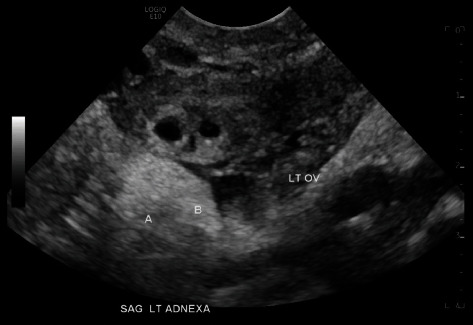

单侧输卵管双胎妊娠的发病率为1/20,000-1/250,000,约有100例报道。在接受药物治疗的六例病例中,有四例取得了成功。一名 24 岁女性因阴道出血和腹部绞痛到急诊科就诊。她的血流动力学稳定,没有急腹症迹象。实验室评估显示她怀孕了,血清中的β-人绒毛膜促性腺激素(b-hCG)为798 mIU/mL。经阴道超声检查(TVUS)发现左侧单侧输卵管妊娠,并伴有卵黄囊。患者选择了以体表面积(BSA)为基础的肌肉注射(IM)甲氨蝶呤(MTX)药物治疗。第4天,患者返回急诊室;她的b-hCG为727 mIU/mL。TVUS 显示双胎左侧输卵管妊娠,卵黄囊和胎儿极无心活动。患者选择继续接受药物治疗,并服用了第二剂基于 BSA 的 IM MTX。第 6 天,患者因腹痛和直肠痛返回急诊室。她的血流动力学稳定,没有急腹症迹象。她的 b-hCG 为 533 mIU/mL。TVUS 显示左侧输卵管持续性双胎妊娠,其中一胎孕龄 5 周,另一胎孕龄 6 周,无破裂迹象。患者继续接受连续的 b-hCG 检查。在首次服用 MTX 31 天后,她的 b-hCG 为

The incidence of unilateral tubal twin pregnancy is 1/20,000-1/250,000 with about 100 reported cases. Four of the six cases that were medically managed were successful. A 24-year-old female presented to the emergency department (ED) with vaginal bleeding and abdominal cramping. She was hemodynamically stable without signs of an acute abdomen. Laboratory evaluation revealed she was pregnant with a serum beta-human chorionic gonadotropin (b-hCG) of 798 mIU/mL. Transvaginal ultrasound (TVUS) revealed a single left tubal pregnancy with a yolk sac. The patient elected medical management with body surface area (BSA)-based intramuscular (IM) methotrexate (MTX). On Day 4, the patient returned to the ED; her b-hCG was 727 mIU/mL. TVUS revealed twin left tubal pregnancies with yolk sacs and fetal poles without cardiac activity. The patient elected to continue medical management with a second dose of BSA-based IM MTX. On Day 6, the patient returned to the ED with abdominal and rectal pain. She was hemodynamically stable without signs of an acute abdomen. Her b-hCG was 533 mIU/mL. TVUS showed persistent twin left tubal pregnancies-one at 5 weeks gestational age and the other at 6 weeks gestational age-without evidence of rupture. The patient continued serial b-hCGs. Thirty-one days after the first dose of MTX, her b-hCG was < 1 mIU/mL. TVUS showed resolution of tubal pregnancies. The patient consented to the publication of this case report. This case documents the successful treatment of spontaneous, unilateral tubal twin pregnancies with two-step dosing of IM MTX.